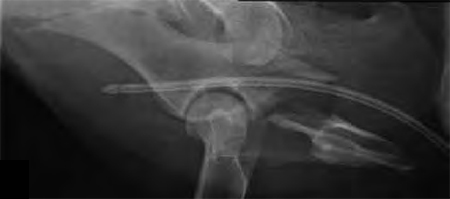

A 4-year-old Gordon setter suffered a road traffic accident and sustained multiple pelvic fractures.

A 7-hole 3.5 mm LC-DCP was applied and two screws were inserted into the sacral body to improve fixation strength in the cranial ilial segment. This bone is quite thin thus note that the screws #1 and #2 are quite short, screws #3 and #4 are the sacral screws and are much longer; the fracture is between screws #4 and #5 (see figure 4a-b)). The opacity on midline in the x-rays is a urinary catheter.